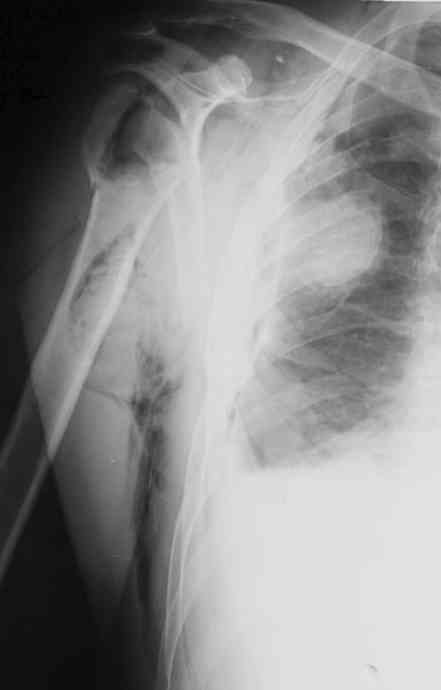

Уважаемые коллеги. Недавно из нашего отделения был выписан пациент 54 лет с закрытым переломом плечевой кости. Из анамнеза: за 2 дня до поступления в НИИСП, в состоянии алкогольного опьянения упал с лестницы на даче (высота 3-4 метра) с упором на правую руку. Через двое суток обратился за медицинской помощью. Доставлен бригадой "Скорой помощи".Правый плечевой сустав умеренно деформирован. По внутренней поверхности плеча имеется кровоподтек. При пальпации плечевого сустава имеется умеренная болезненность. Активные и пассивные движения болезненные. Снижена чувствительность по тыльной поверхности пальцев кисти и отсутствует активное разгибание кисти и пальцев. Имеется подкожная эмфизема шеи, верхней половины грудной клетки (рис 1, 2). На рентгенограмме: оскольчатый перелом головки плечевой кости со значительным смещением, перелом 2-3 ребер справа, тканевая эмфизема (рис 3). КТ при поступлении: перелом головки плечевой кости в области анатомической шейки со смещением отломка головки в грудную полость, правосторонний гидроторакс, перелом 2-3-4 ребер справа. (рис 4). Через двое суток после поступления выполнена операция: атипичная торакотомия, эвакуация свернувшегося гемоторакса, удаление инородного тела (головки плечевой кости) из плевральной полости (при этом выявлено имеющееся повреждение париетального и висцерального листков плевры) (рис. 5), дренирование плевральной полости, замещение проксимального конца плечевой кости спейсером из костного цемента с антибиотиком (рис. 6). Послеоперационный период протекал гладко. При контрольной рентгенографии положение спейсера удовлетворительное (рис. 7, 8). Дренаж из плевральной полости удален через 3 суток после вмешательства. Послеоперационная рана зажила первичным натяжением. Через 12 дней после операции больной выписан на амбулаторное лечение.

Александр, спасибо за столь высокую оценку. Нисколько не сомневаюсь, что и нам есть чему у Вас поучиться. Для иллюстрации прилагаю сегодняшний снимок с нашего обхода в шоковом зале реанимации (рис. 2).